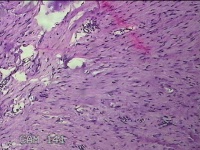

左耳新生物

性别

女

年龄

23岁

临床诊断

纤维瘤?

一般病史

左耳皮肤起新生物2年。

标本名称

大体所见

灰白暗红色组织1.8x1.5x0.7cm,表面光滑,切面灰白粉红色,质软。

良性病变。